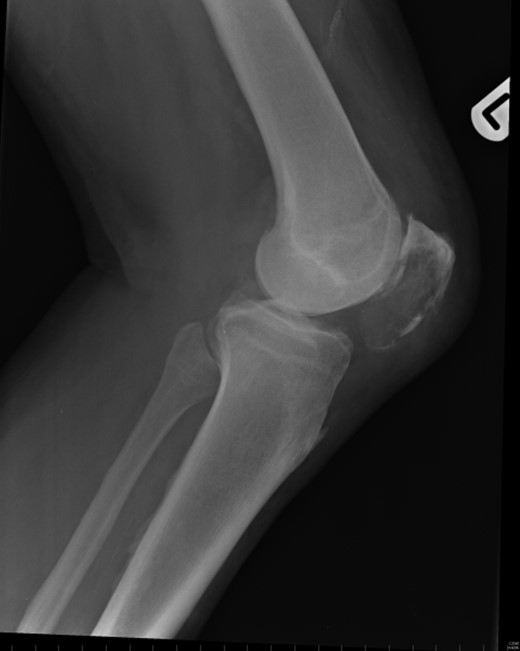

Repeat radiographs performed by his general practitioner 19 months after initial presentation (Figs 4–6) revealed a large lucency within the patella and a discontinuity in the anterior cortex of the inferior pole suggesting pathological fracture. A bone scan was arranged and demonstrated isolated abnormal tracer activity around the left patella (Fig. 7). Due to the pacemaker a computed tomography (CT) scan was performed to further characterize the lesion. This confirmed a large lucent area occupying most of the patella with multiple areas of cortical disruption along its anterior border (Fig. 8). Since the exact nature of the lesion could not be determined an ultrasound-guided biopsy was suggested but ultrasound screening revealed the lesion to be highly vascular (Fig. 9). In view of this the radiologist performed a renal ultrasound, which revealed a large mass arising from the superior pole of the left kidney. Subsequent CT of the chest, abdomen and pelvis followed demonstrating the extent of disease. There was a large (13 × 8.5 × 9 cm) mass arising from the superior pole of the left kidney (Fig. 10), the appearances of which were consistent with a primary RCC. Metastases were found in both adrenals and lungs, but no other bone metastases. Since diagnosis, the patient has had a left nephrectomy and is currently receiving radiotherapy and zolendronic acid treatment for the patella metastasis. At the time of writing this report the patient's patella lesion continues to be managed non-operatively.

The absence of associated features of systemic disease, as well as radiographic appearances in keeping with early patello-femoral osteoarthritis (OA), account for the delay in diagnosis. The initial images suggest mild degeneration but, whilst subarticular cysts are a radiographic feature of OA, the lesion shown in this case is larger than would be expected with the level of disease shown elsewhere in the joint.